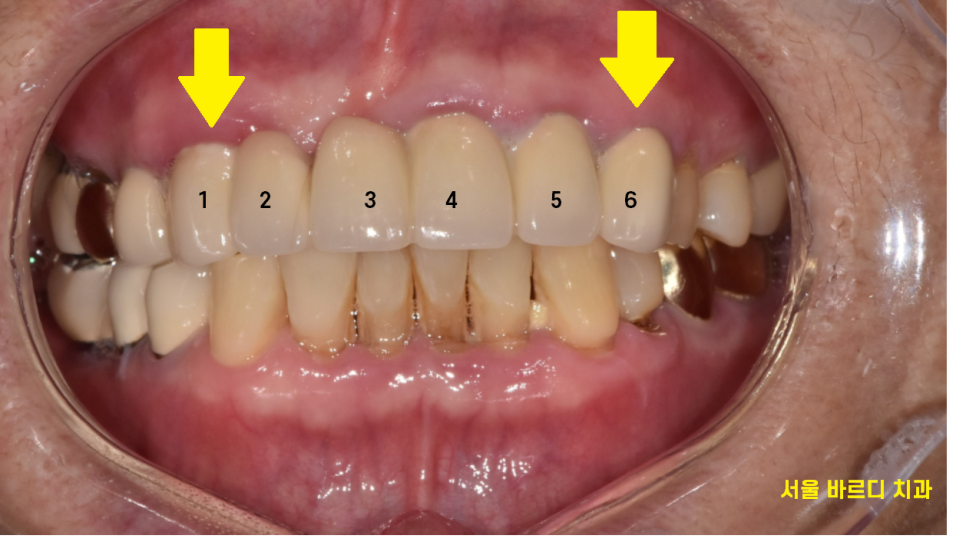

24.07.31

6개의 앞니 임플란트 브릿지로 완성해드렸습니다.

자연치 상태에서는 4개 치아가 6개의 치아 힘을 분산했는데

앞니 브릿지 교체하면서

임플란트는 3개만 심어드렸습니다.

1개의 비용을 덜어드린 셈이죠.

앞니는 노출이 많이 되기에

주변 치아와 자연스럽게 어우러져야하는데요.

티가 나지 않게

자연스러운 미소를 만들어드리는 서울바르디치과입니다.